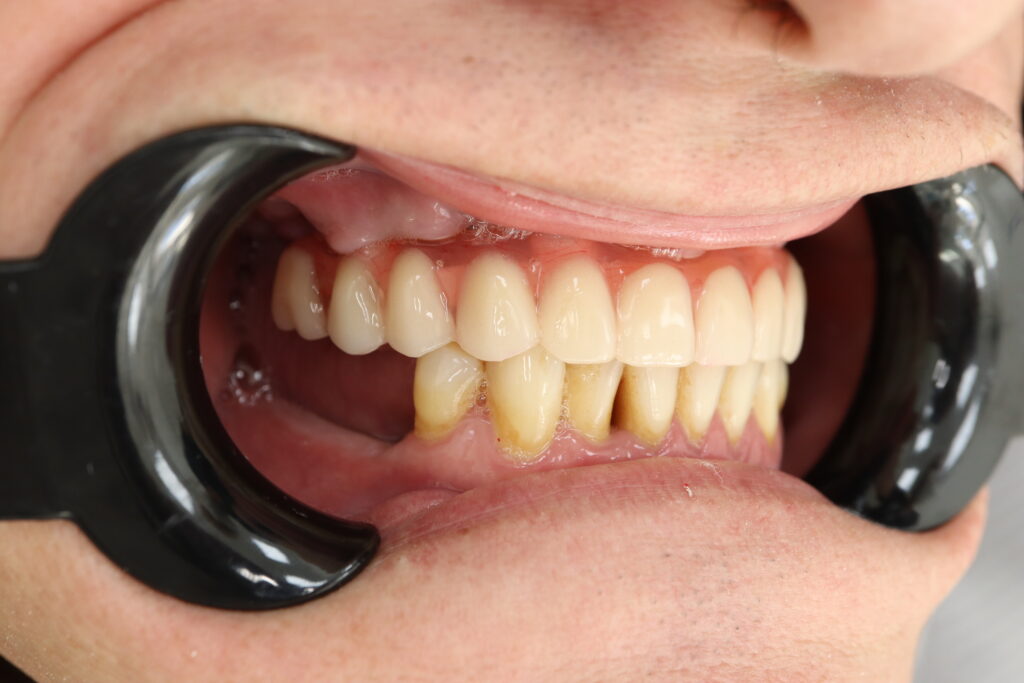

Ситуация до лечения

Жалобы: Пациент обратился к нам с целью проведения комплексной имплантации верхней челюсти.

Диагноз: Частичная вторичная адентия верхней челюсти.

пациент до протезирования